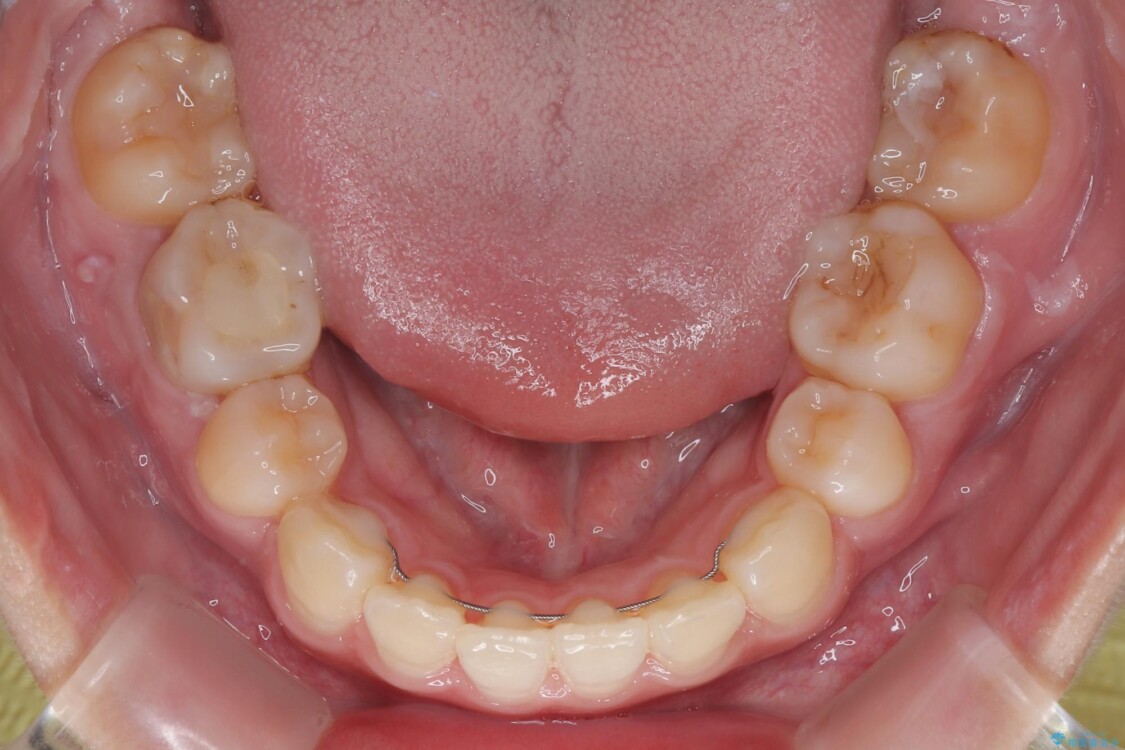

治療前

• 転勤でも安心して治療継続 抜歯スペース閉鎖と深い噛み合わせ改善のワイヤー矯正 治療前画像